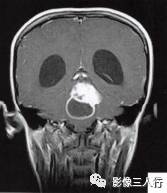

(二)影像所见

头颅MRI扫描示:小脑上蚓部见团块状异常信号影,边缘清楚,大小约4.5cm×3.5cm×3.7cm,T1WI(图B)等信号,中心可见更低信号,T2WI(图A)呈髙信号,水抑制(图C) 等信号,中心呈更低信号,周边可见轻度高信号水肿区。增强后(图D〜F)病灶可见明显环形强化,壁较厚,内壁欠光滑,邻近小脑及第四脑室受压,第三脑室、双侧脑室扩张积水。

诊断:小脑上蚓部占位,考虑肿瘤性病变,以毛细胞型星形细胞瘤可能性大。